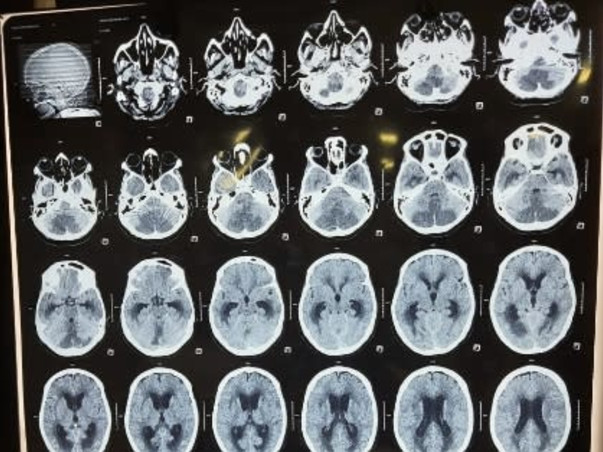

My mother has suffered a Brain Stroke. She is currently admitted and receiving medication & treatment at Apex Super Speciality Hospital, Varanasi. She has undergone one surgery till now.

She need to go through another major operation to remove blood clotting from the brain. Hence in the next few days, we need Rs.5,00,000 more for further treatment. Please come forward to support my cause. Any contribution will be of immense help. Do contribute and share this crowdfunding fundraiser link with your friend's and family.